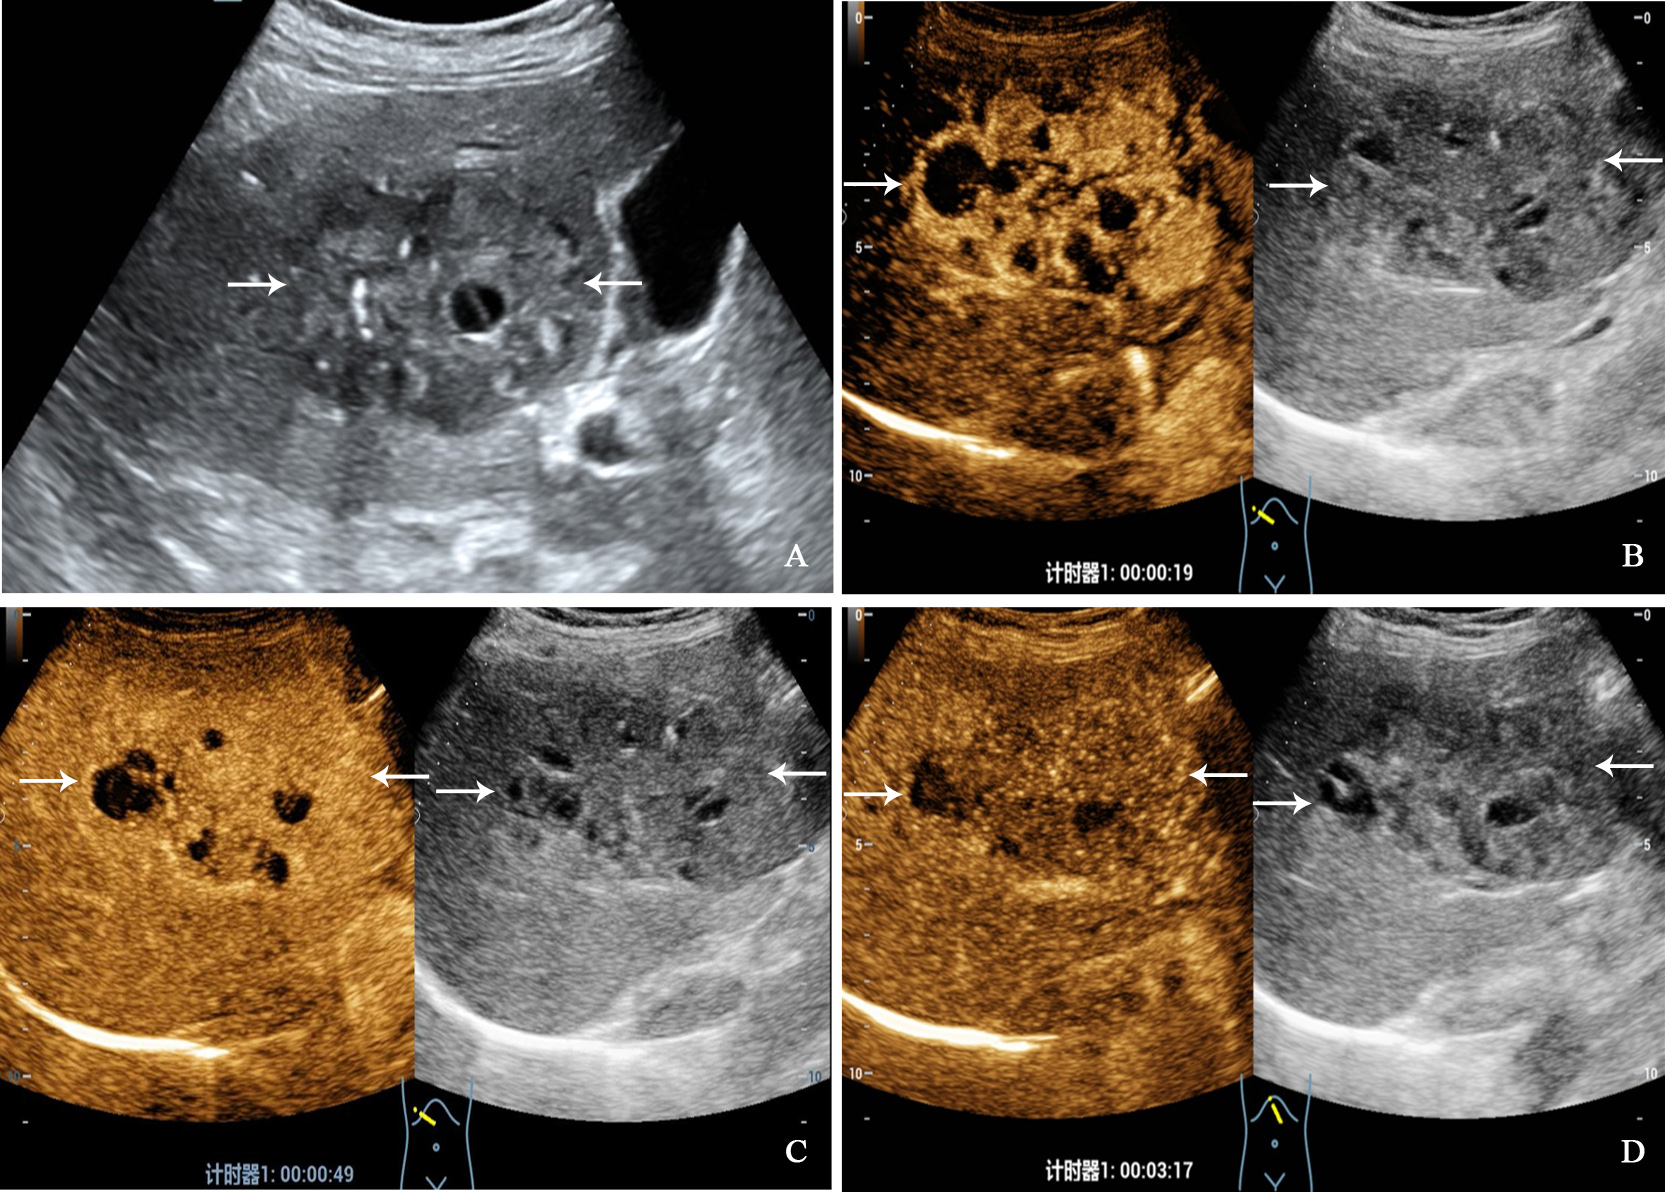

Figure 2

A 68-year-old woman with primary neuroendocrine tumor. The patient had no underlying liver disease. Conventional ultrasound showed that a mixed echoic tumor with focal calcification and largest diameter of 10.0 centimeters in anterior segment of the liver (A). In the arterial phase of contrast-enhanced ultrasound, the tumor showed heterogeneous hyperenhancement (B), and began washout before 60 seconds (C). hypoenhancement in the late phase (D).